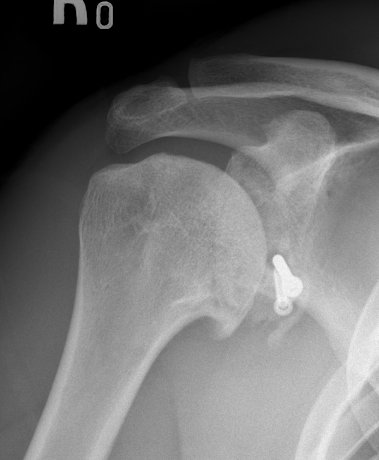

Bone block positioning

Concepts

- coracoid must not overhang medial to avoid osteoarthritis

- coracoid < 5 mm medial to glenoid rim

- coracoid lower half of glenoid 2 - 5 o'clock

- fixation screws purchases posterior glenoid cortex

- screws do not penetrate articular surface

Secure coracoid

- inferior half of glenoid

- no medial overhang

- secure with 2 x bicortical screws with compression